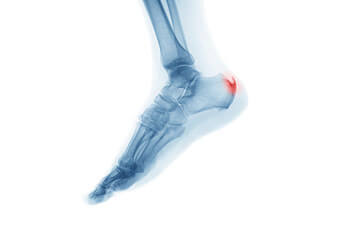

Heel spurs are essentially a hook of bone that forms at the back of the foot, at the base of the ankle. Heel spurs are also described as a calcium deposit that covers the tendons and ligaments of the ankle. Heel spurs cause extreme pain, and can prevent someone from walking or being physically active at a normal level.

The symptoms of heel spurs are pain in the lower ankle, which increase when walking. Treatment of heel spurs can be treated many ways and most often times is very effective. If someone suspects that they have heel spurs, they should contact their physician. Their physician will recommend that they perform an x-ray on the patient's ankles. The physician may also perform a physical on the patient to ensure that there are no underlying conditions, and of course if heel spurs are discovered a physician can recommend treatment options.